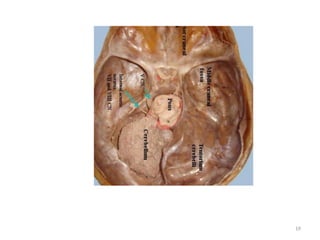

• Da região da cabeça, a área mais estuda é o

encéfalo, que pode ser acometido de várias

patologias associadas a traumas, patologias

REVISÃO ANATÔMICA

12

vasculares, tumorais, deformidades e do

sistema nervoso central.

• Trata-se de uma região com grande riqueza

anatômica, necessitaríamos de muito tempo

para discutir todas. Vamos elencar as mais

importantes no desenvolvimento do exame.